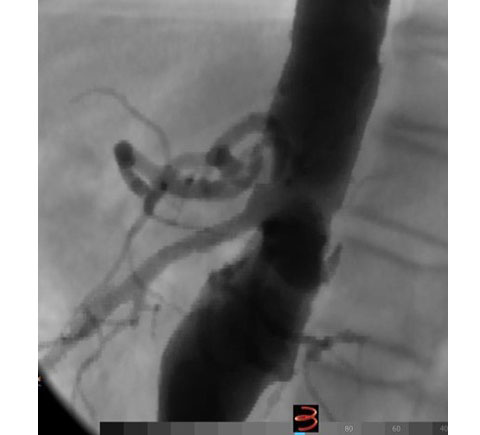

Περίπτωση 3

Άνδρας ασθενής 65 ετών με ανεύρυσμα κοιλιακής αορτής μέγιστης διαμέτρου 5,8 εκατοστών που αρχίζει αμέσως κάτω από τις νεφρικές αρτηρίες (παρανεφρικό), παχύσαρκος, με πολλαπλές συνοδές παθήσεις που αποκλείουν την ανοιχτή χειρουργική αποκατάσταση, η οποία με την σειρά της παρουσιάζει σημαντική πιθανότητα για μετεγχειρητικές επιπλοκές

Αντιμετωπίστηκε ενδαγγειακά με την τεχνική χρησιμοποίησης εξατομικευμένου μοσχεύματος τύπου Zenith με πλάγιες οπές (fenestrations), στις 2 νεφρικές αρτηρίες και την άνω μεσεντέριο αρτηρία με επιπρόσθετη ευρεία εγκοπή (scallop) για την κοιλιακή αρτηρία, το οποίο σχεδιάστηκε αποκλειστικά για την περίπτωση του